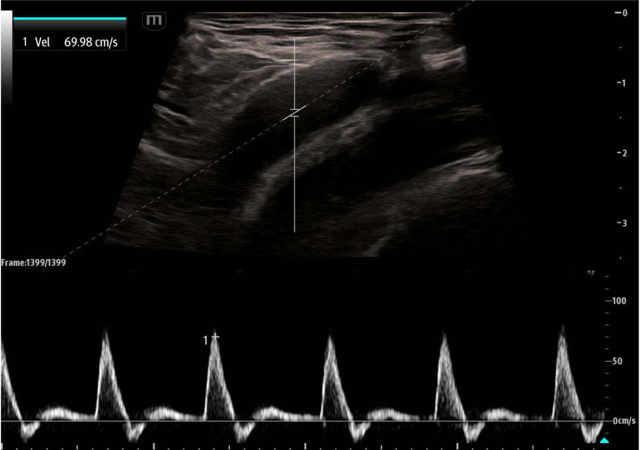

While the use of compression and color doppler aim to provide a qualitative assessment of pulsatile flow, pulsed wave doppler (PWD) of the large arteries can provide both qualitative and quantitative assessment of blood flow. Using the PWD mode, a sampling gate is centered within the artery in long axis and flow is measured. Most research thus far has focused on the peak systolic velocity (PSV) and end diastolic velocity (EDV), with more limited study of mean diastolic velocity (MDV).

The proof of concept was first published in 2015 by Adedipe et al who showed doppler measurements of carotid blood flow during cardiac arrest was feasible.11 Measurements were obtained by trained emergency physicians and investigators were able to complete a scanning protocol that included both color doppler and pulsed wave doppler measurements (PSV, EDV, MDV). Cohen et al. followed this in 2022 and showed pulsed wave doppler of the femoral artery was more accurate than manual palpation at either the femoral or carotid artery (95.3% vs. 54.0%; p < 0.001) across 213 pulse checks in 54 patients.12 A secondary outcome of that same study showed that a PSV ≥ 20 cm/s accurately detected an arterial line pulse SBP ≥ 60 mmHg with an accuracy of 91.4% and area under the receiver operating curve = 0.975. Lastly, in 2023, Haddad et al. showed the diagnostic accuracy of this same PSV cut off (≥ 20 cm/sec) for detecting ROSC with SBP of 60 mmHg was 89% (95% CI: 82%-94%) versus 59% (95% CI: 49%-68%) and 58% (95% CI: 48%-67%) for ETCO2 20 and 25 mmHg.13

May2025Sonographic Fig 3 psv pulse check.pngImage 3. Pulsed wave doppler of the femoral artery in long axis showing a PSV of approximately 70 cm/sec.

Femoral artery POCUS showed a pulsatile, noncompressible vessel. PWD gates were placed over the vessel and demonstrated a PSV of 22 cm/s. CPR was halted and instead push-dose epinephrine was administered in 2- to 4-mcg aliquots every 30 seconds. After 15 mcg of epinephrine, the patient regained a mean arterial pressure of 65 mm Hg and palpable peripheral pulses. The patient was started on continuous norepinephrine, admitted to the ICU, and subsequently discharged home neurologically intact 16 days later. Case adapted from Simard et al. (2019).28